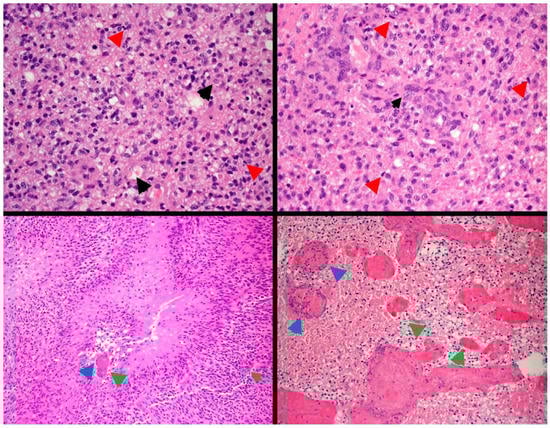

2. Glioblastoma: Origin, Histology and Classification